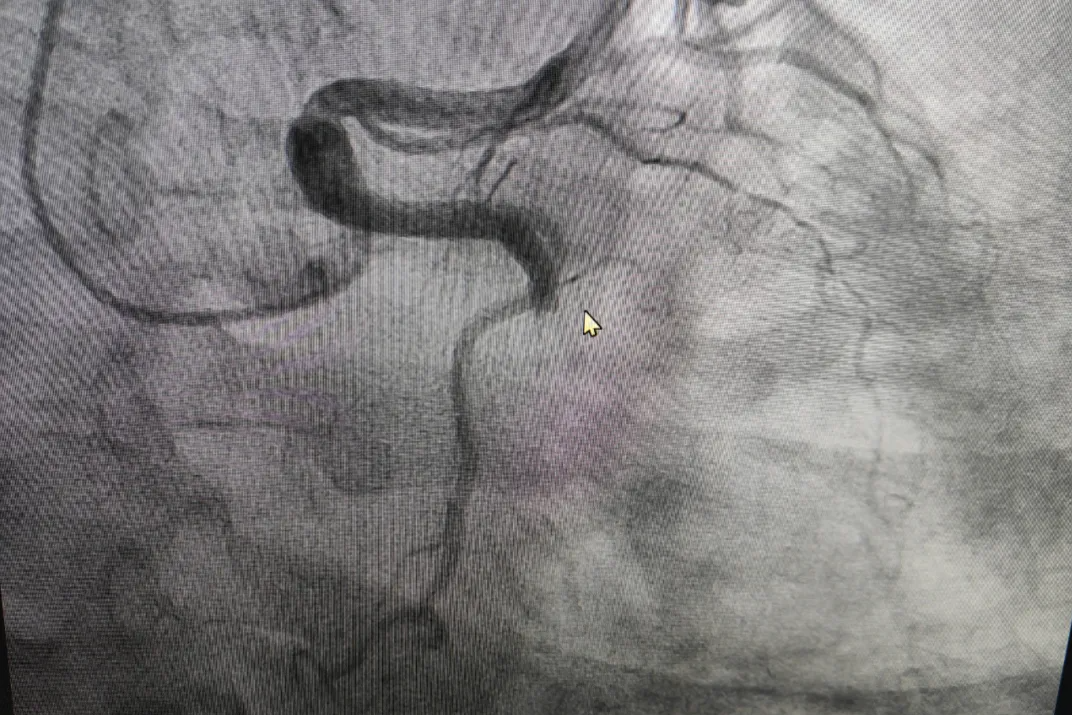

「喷射性咯血!医生临危不乱,微创介入化险为夷」